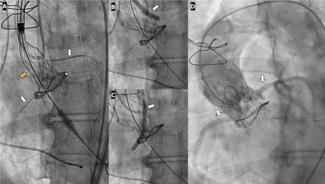

First, you're talking about operators that were very experienced with Sentinel, and they were actually using Emboliner for the first time—centers were allowed up to 2 roll-ins but, for the most part, this was a brand new device. So, of course they're going to take a little bit more time placing the device. You're also in a trial where there was a core lab that wanted to look at, for instance, whether all the vessels were covered at the time of valve deployment, so there were additional fluoroscopic views that people were asked to obtain. So, when you look at a continuous variable like fluoroscopy time, sure, they're going to be statistically significant, but there really wasn't much clinically significant difference in terms of contrast volume, fluoroscopy time. Overall procedural lengths were the same, the device dwell times were about the same. So, I wouldn't necessarily think that's going to factor in too much for a structuralist, as there's always a learning curve to a new device.

But what was interesting was the technical success—meaning, were the intended vessels covered at the time of valve deployment? It was much higher with the Emboliner because the device just drapes across the arch, you don't actually have to get the baskets in the great vessels. Plus, it comes from the legs, you don't have to deal with tortuosity in the arms. So technical success was much higher.